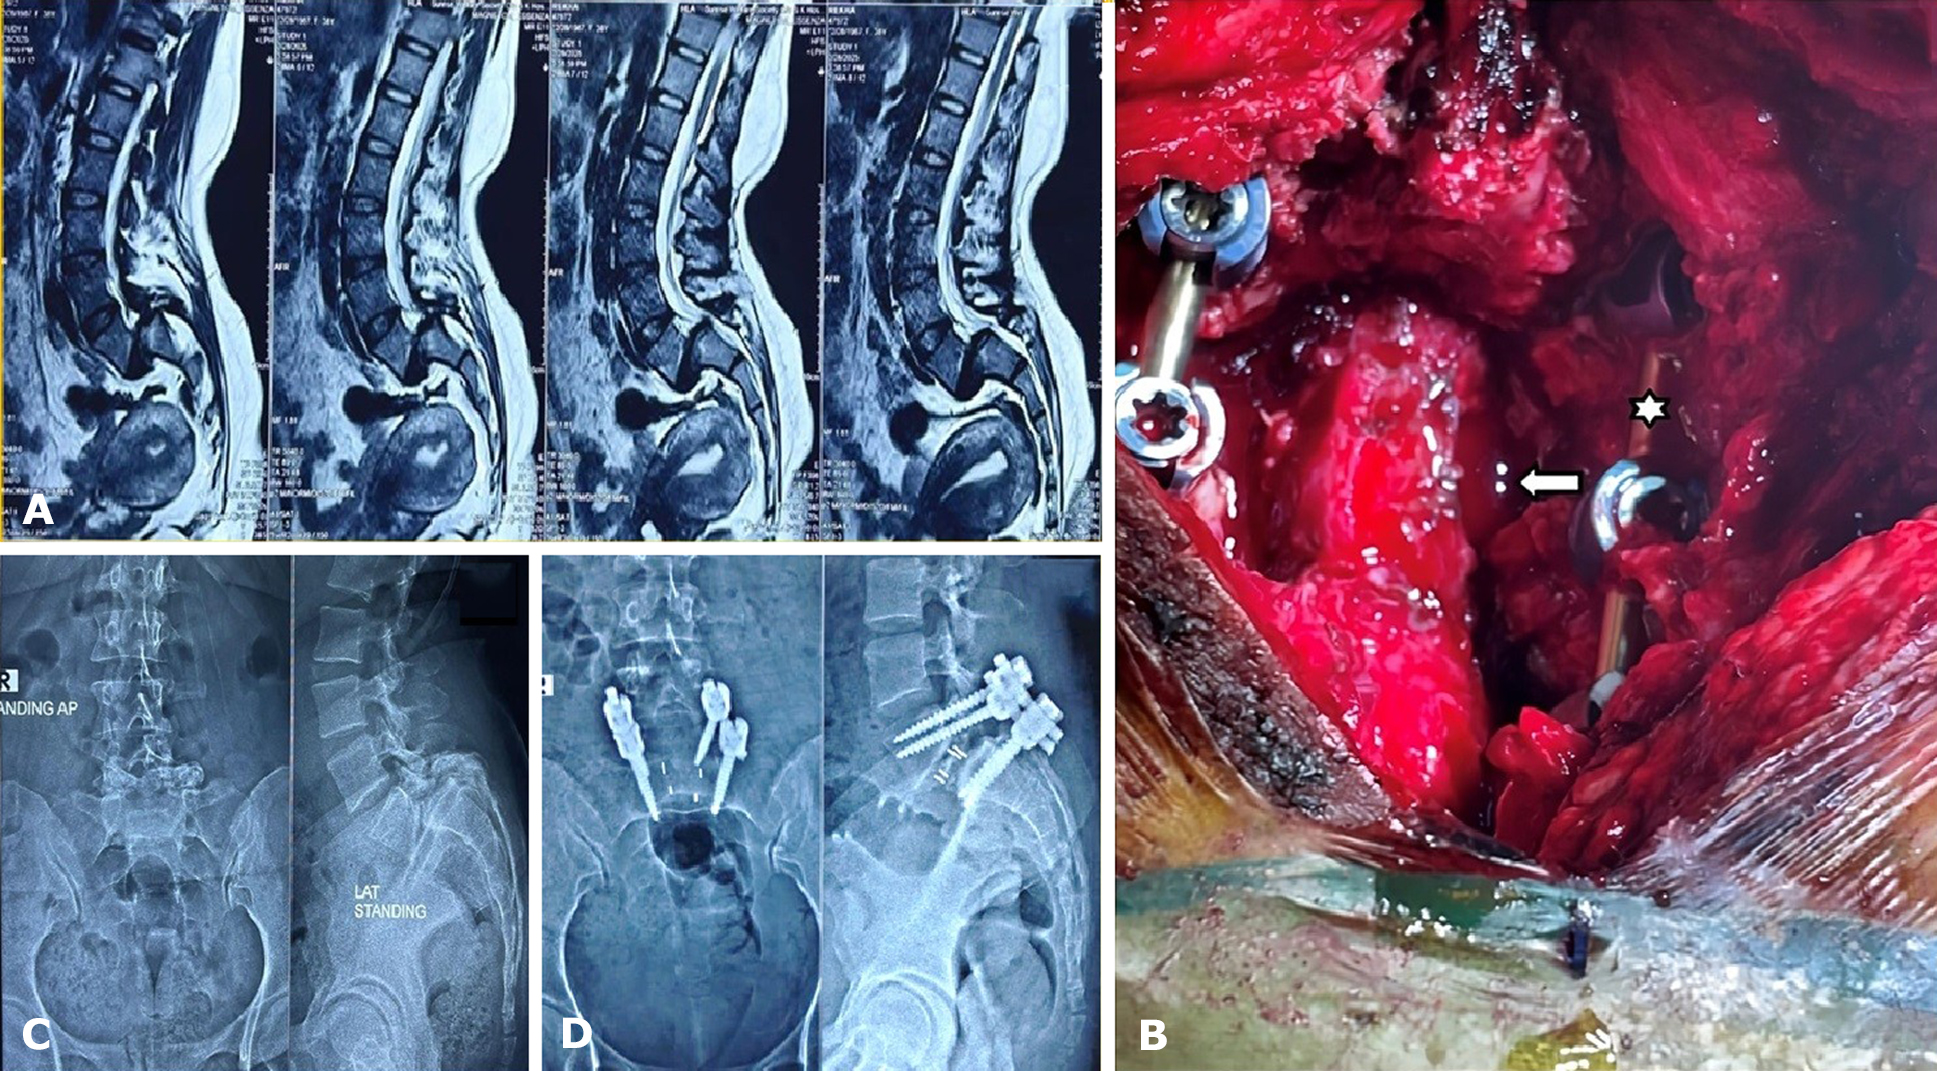

Each patient underwent a thorough pre-anesthetic evaluation and fitness assessment. All patients in the study underwent open TLIF surgery. Additionally, reduction was performed in all high-grade spondylolisthesis cases to restore alignment. Operative steps included a midline posterior incision with subperiosteal exposure of the relevant spinal levels, followed by decompression of neural elements through laminotomy and foraminotomy as needed. The intervertebral disc space was then prepared with thorough disc removal, after which interbody fusion was performed using appropriately sized cages combined with autologous or local bone graft. Pedicle screw fixation with rods was employed to achieve spinal stabilization (Fig. 2). Adequate hemostasis was achieved, and the wound was closed in layers, with the placement of a suction drain as indicated. Intraoperative parameters, including blood loss, duration of surgery, complications, and the level of fusion, were carefully documented.

Fig. 2. A case study of grade 4 spondylolisthesis. Panel A – MRI of the lumbosacral spine (T2-weighted sagittal images) demonstrates lumbar spondylolisthesis with associated prolapsed intervertebral disc at the L4-L5 level. Panel B – Intraoperative photograph displaying laminotomy (solid white arrow) and placement of a pedicle screw rod construct (solid white star). Panel C – Plain X-rays of the lumbosacral spine (AP and lateral views, preoperative images) show loss of alignment due to spondylolisthesis. Panel D – Postoperative plain X-rays (AP and lateral views) illustrate the pedicle screws, rods, and interbody cage in situ, confirming realignment and stabilization

Patients were mobilized early with lumbar support. Postoperative radiographs were performed to confirm implant placement (Fig. 2). Analgesia, physiotherapy, and gradual rehabilitation were provided. Patients were discharged after achieving ambulation with adequate pain relief. Follow-up evaluations were carried out at 1 month, 3 months, and 6 months. Both outpatient visits and telephonic consultations were utilized when in-person visits were not possible.